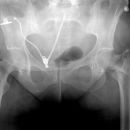

Open Book Fracture